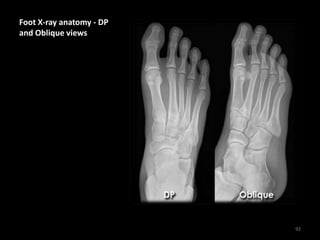

Foot X-ray anatomy - DP

and Oblique views

90

• Hindfoot = Calcaneus +

Talus

• Midfoot = Navicular +

Cuboid + Cuneiforms

• Forefoot = Metatarsals

+ Phalanges

• 1 = Hind-midfoot

junction

• 2 = Mid-forefoot

junction =

Tarsometatarsal joints

(TMTJs)

91

92

Metatarsals and phalanges

of the toes are numbered 1

to 5

1 = Big toe

5 = Little toe

MC = Medial Cuneiform

IC = Intermediate

Cuneiform

LC = Lateral Cuneiform

93